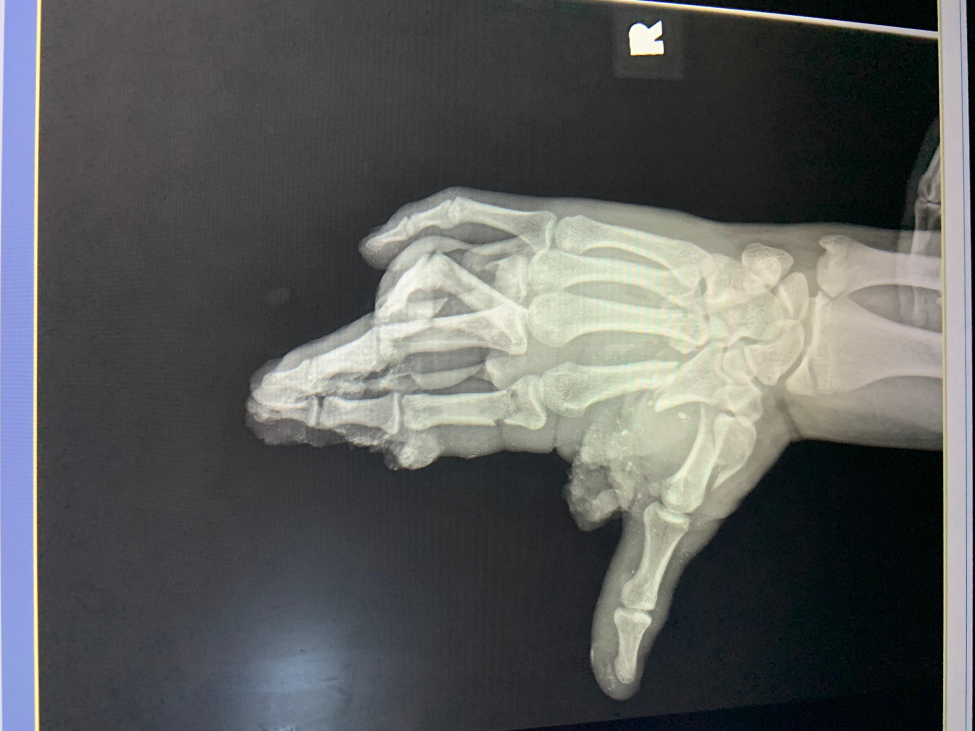

X-ray of Tanner’s hand prior to surgery. (Photo provided by doctor)

Tanner’s surgery with Mansour lasted 8 ½ hours and ultimately required nine screws and four pins. Much of the time involved debridement, which is removing dead and dying tissue. After the wound was as clean as possible, Mansour began to stabilize the bones.